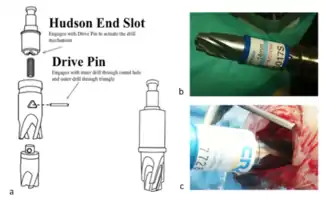

A technical drawing of the clutch mechanism of a "perforator" drill bit

A technical drawing of the clutch mechanism of a "perforator" drill bit

Burr holes may be used for epidural and subdural hematomas, and surgical access for certain other neurosurgical procedures, such as intracranial pressure monitoring or microvascular decompression. When multiple burr holes are used to remove a piece of skull it is known as a craniotomy. Trepanation instruments, nowadays being replaced with cranial drills, are now available with diamond-coated rims, which are less traumatic than the classical trephines with sharp teeth. They are smooth to soft tissues and cut only bone.[5] Additionally, the specially designed drills come with safety feature prevents the drill from penetration into the brain tissue (through the dura mater).